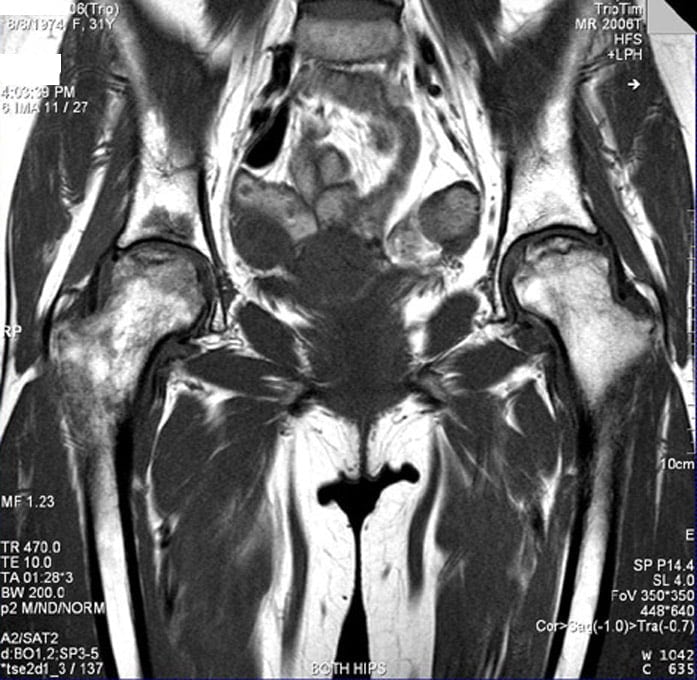

С помощью магнитно-резонансной томографии выявляют патологические изменения в костях, суставных хрящах, сумке, связках, нервах, сосудах и периартикулярных тканях. При правильной интерпретации исследование позволяет поставить диагноз без каких-либо дополнительных диагностических мероприятий. Давайте посмотрим, что показывает томография тазобедренных суставов при разных заболеваниях.

| Асептический некроз головки бедренной кости | На первой стадии болезни в головке бедренной кости выявляют локальный гиподенсивный участок с возможной каемкой умеренного склероза. На следующих стадиях на МРТ-граммах появляются некротические дефекты, участки секвестрации, кисты и т.д. Асептический некроз ІІ-V стадии можно диагностировать даже с помощью рентгенографии |

| Деформирующий остеоартроз | На I-II стадиях заболевания у человека разрушаются суставные хрящи. Патологические изменения выявляют с помощью УЗИ или МРТ. При исследованиях они визуализируются в виде дефектов хрящевой ткани. В дальнейшем в патологический процесс вовлекаются кости, а диагностировать болезнь помогает обычная рентгенография |

| Болезнь Бехтерева | МРТ позволяет выявить патологические изменения в субхондральной кости, характерные для начальных стадий коксита. С помощью УЗИ обнаружить их невозможно. В дальнейшем заболевание вызывает утолщение капсулы ТБС и скопление жидкости в синовиальной полости. Эти изменения можно обнаружить с помощью более доступных методов, чем этот |

| Коксартрит | Проявляется отеком и утолщением суставной капсулы, воспалением ТБС, скоплением жидкости в синовиальной полости. Выявить эти изменения можно с помощью МРТ или УЗИ. Косвенные признаки артрита можно обнаружить и на рентгенограммах |

| Дисплазия ТБС у детей | На МРТ при дисплазии выявляют заворот хрящевой губы, гипертрофию поперечной связки, деформацию суставной капсулы и ее сдавление сухожилием подвздошной мышцы. Магнитно-резонансная томография позволяет получить пространственное изображение структур ТБС, что очень важно в планировании лечения патологии |

| Переломы шейки бедра, вывихи ТБС | Диагностируются с помощью обычной рентгенографии, которая выявляет нарушение целости костей или их смещение. Исследование используют для оценки состояния мягких тканей, нервов и сосудов тазобедренного сустава. Это позволяет понять, насколько тяжелое состояние пациента |